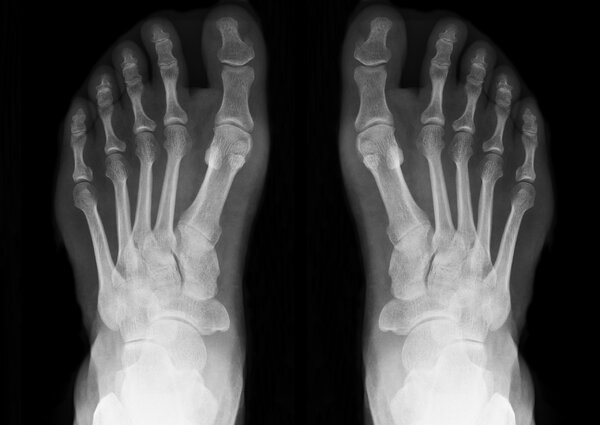

Mi közismertebb nevén a patella?

Forrás GETTY IMAGES

3 9

Combcsont

Sípcsont

Szárkapocscsont

Térdkalács

Magyarázat

Ez bizony a térdkalács.